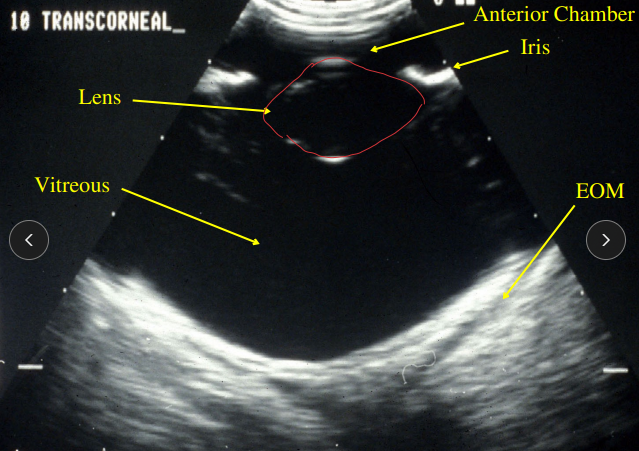

Ultrasound

Why: when the posterior segment cannot be visualized - blood or cataracts

Lens, vitreous, retina, optic nerve, and uveal tract

Detects: Lens luxation, Retinal detachment, tumors, uveal cysts, hemorrhage, cataracts